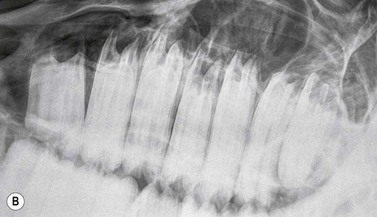

Fig. 13.20 (A) Intra-oral radiograph of a maxillary cheek teeth row.

Radiograph courtesy of J. Easley.

image